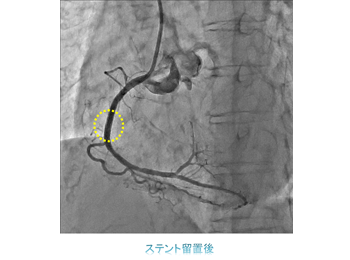

一方治療には、狭くなった冠動脈にステントを留置する冠動脈ステント留置術(PCI)をはじめ、心臓以外の動脈や静脈を拡張させる血管拡張術(PTA)、頻脈性不整脈の原因となる電気回路を遮断させるため、心筋に高周波電流を流して焼灼するアブレーションや、徐脈性不整脈に対するペースメーカー埋込術(PMI)、除細動器のデバイス埋め込み術(ICD)などがあります。

ハイブリット手術室では経皮的大動脈弁置換術(TAVI)、経皮的僧帽弁クリップ術(MitraClip)、左心耳閉鎖術(WATCHMAN)などの構造的心疾患(SHD:Structure Heart Disease)に対するインターベンションをはじめ、大動脈解離や大動脈瘤に対するステントグラフト内挿術(TEVAR、EVAR)、エキシマレーザーを用いたデバイスリード抜去術など、様々な手技を行っています。